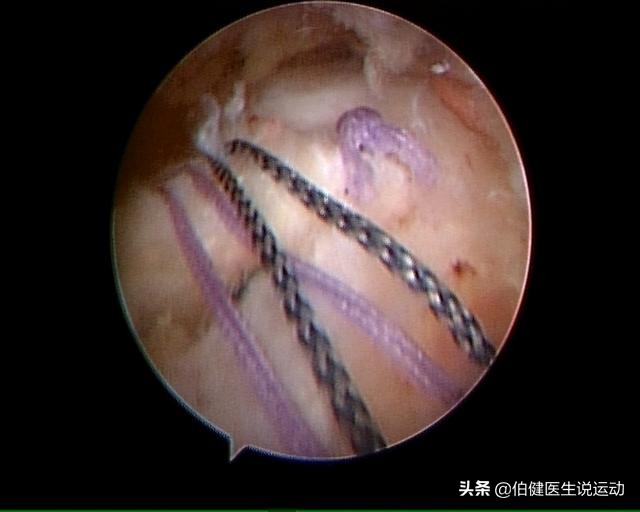

通过关节镜手术证实,肩袖磨损了,予以清除骨棘,缝合肌腱。

肩袖磨损撕裂

镜下微创缝肌腱